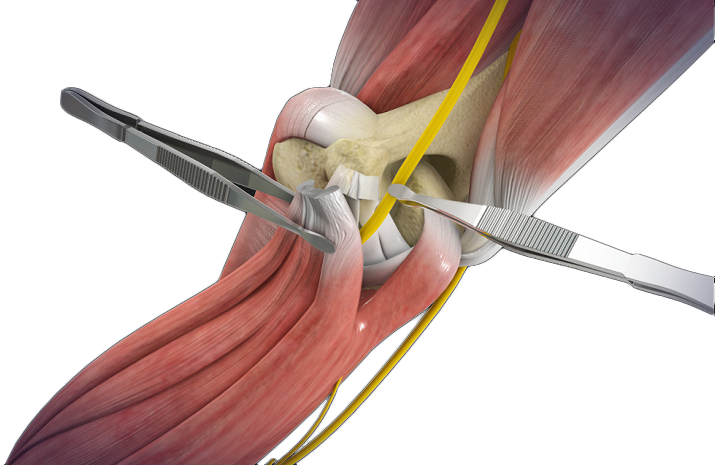

Distal Biceps Repair

The biceps is a large muscle located in the front of your upper arm and runs from the shoulder to the elbow joint.

Biceps Tendon Repair

Biceps tendon repair is a surgical procedure to restore a biceps tendon that has been torn or ruptured by severe trauma or injury.